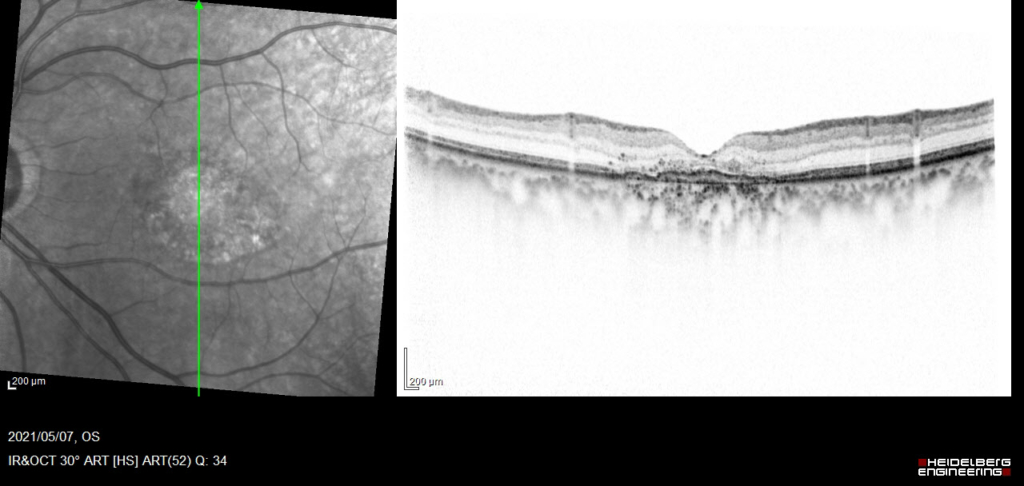

中心窩に灰白色病変がみられる。

漿液性網膜剥離 Serous Retinal Detachment(SRD)がみられる。RPEは不正に隆起し、double-layer sign(RPEを示す高反射層とそれより外層にみられる高反射層の間に間隙がみられる)がみられ、CNVの存在を示す。